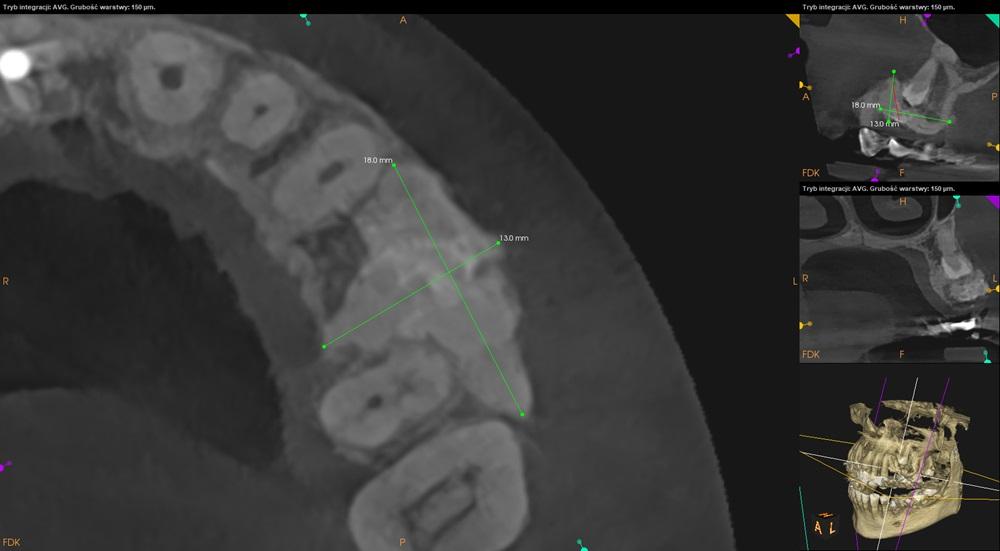

Pacjentka: wiek 52 l.

Badanie z dnia: 10.11.2023

Badanie wykonano na aparacie: Carestream CS 9600

Parametry techniczne badania: 120kV, 6,3mA, 20s 1147mGy*cm²

ANALIZA BADANIA

Ząb 24 – częściowo zatrzymany – nie pokryty kością po stronie przedsionkowej. Położony skośnie, koroną skierowany w stronę mezjalną. Wierzchołki korzeni zagięte, w świetle zatoki szczękowej.